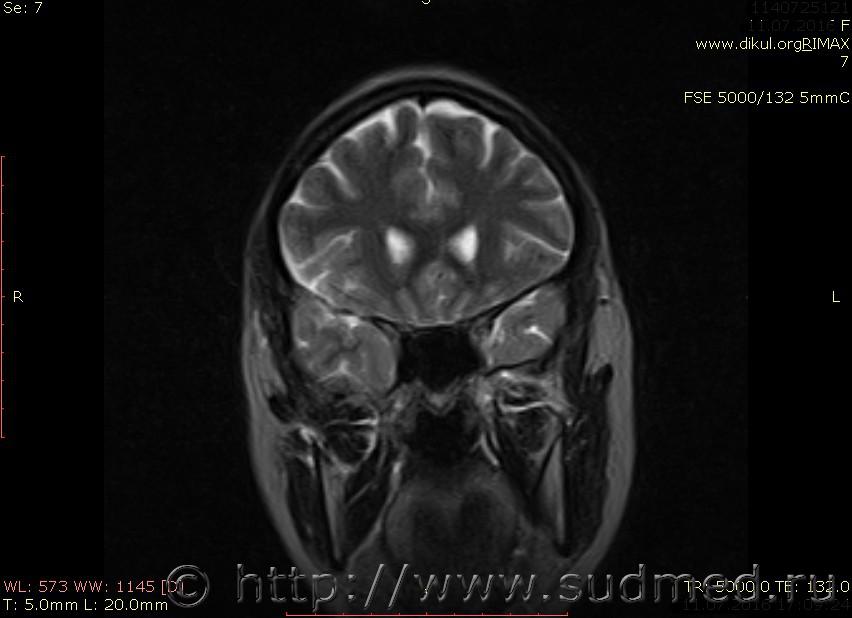

МРТ головного мозга показало: МР-данных за наличие очаговых изменений в веществе головного мозга на момент исследования не выявлено. МР-признаки нарушения соотношения в атланто-осевом суставе. Определяется ассиметрия положения зубовидного отростка С2 относительно боковых масс С1(справа 6,5; слева 4 мм.)

Сама по себе эта информация даёт основания подозревать вывих первого шейного позвонка, но однозначно не свидетельствует о наличии вывиха. Нужно смотреть на снимках наличие реакции со стороны мягких тканей, в т.ч. связочного аппарата, нужно анализировать особенности неврологической патологии, её динамику и проч.

Запрошен электронный вариант снимков из учреждения, где делалось МРТ. Т.к. с самого снимка делать копии не получается,очень мелкие кадры. Завтра попробую вставить в сообщение. (Но СМЭ снимок не смотрел, смотрел только мед.карту, в которой находилось описание МРТ).

Посмотрите пожалуйста снимки, надеюсь на них видны позвонки С1,С2?

Прошу прощения, попробую снова прикрепить файлы. Данные учреждения и пациента убраны.